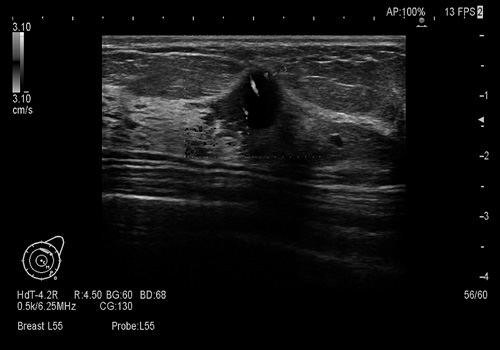

超音波とは高濃度乳房でもよく見えるが…

超音波を出すプローブ(器具)を乳房に乗せて動かし、反射してくる超音波を画像として見る検査。マンモのような放射線被曝もないので、妊娠中でも検査可能。若い世代に多い高濃度乳房でも、しこりがよく見える。

発見率は高いが、がんではないしこりも見つけてしまう可能性もある。乳がん検診に使用するための科学的根拠(エビデンス)がまだない。

上半身裸になってあお向けに寝てゼリーを塗った乳房にプローブを当てゆっくり動かす。鎖骨、わきの下のリンパ節もよく見る。

超音波で見える画像。中央に丸く見えるのが、がんのしこり。若い世代の乳房でもよく見える。